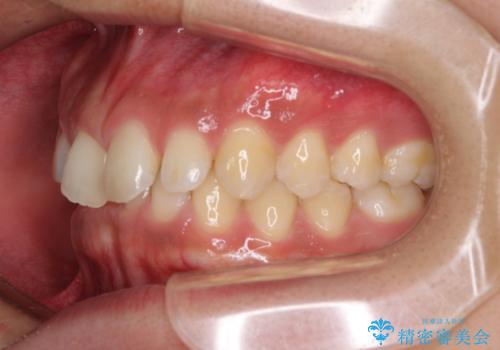

デコボコとディープバイトを治したい インビザラインによる矯正治療

- 前歯のデコボコや隙間と深い咬み合わせ(ディープバイト)を気にして来院された患者様です。

インビザラインによる上下歯列の側方拡大と後方移動、IPR(歯と歯の間を削る)にるスペースの獲得により、デコボコとディープバイトを改善することとしました。

気になっていたデコボコや隙間は改善し、きれいな歯列に整えることができました。

咬合力が非常に強い方であったため、これ以上のディープバイトの改善は困難となりました。